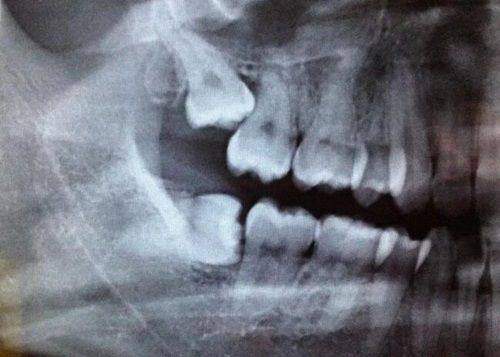

深圳鼎植口腔拥有VIIV缺骨植技术,针对牙槽骨重萎缩、传统种植无法实施的患者,通过将种植体直接固定于颧骨和翼板,无需植骨等待,实现“当天种牙、当天戴牙、当天进食”。该技术采用3D导航和动态导板,误差控制在0.1毫米内,更准避开神经血管;微出血、创伤小,术后3年植体稳固性依旧出色。还有半口速齿种植,创新运用冷焊接技术,实现手术与修复同步进行,一次半口固定手术,当天戴牙当天用,相比传统All - on - 4/6技术,总费用仅为60%(半口约5万元)。数字化微创种植配备智能化口腔CT、种植导航系统、iTero口扫仪等设备,通过三维建模更准定位种植点,减少手术创伤,缩短复原周期。